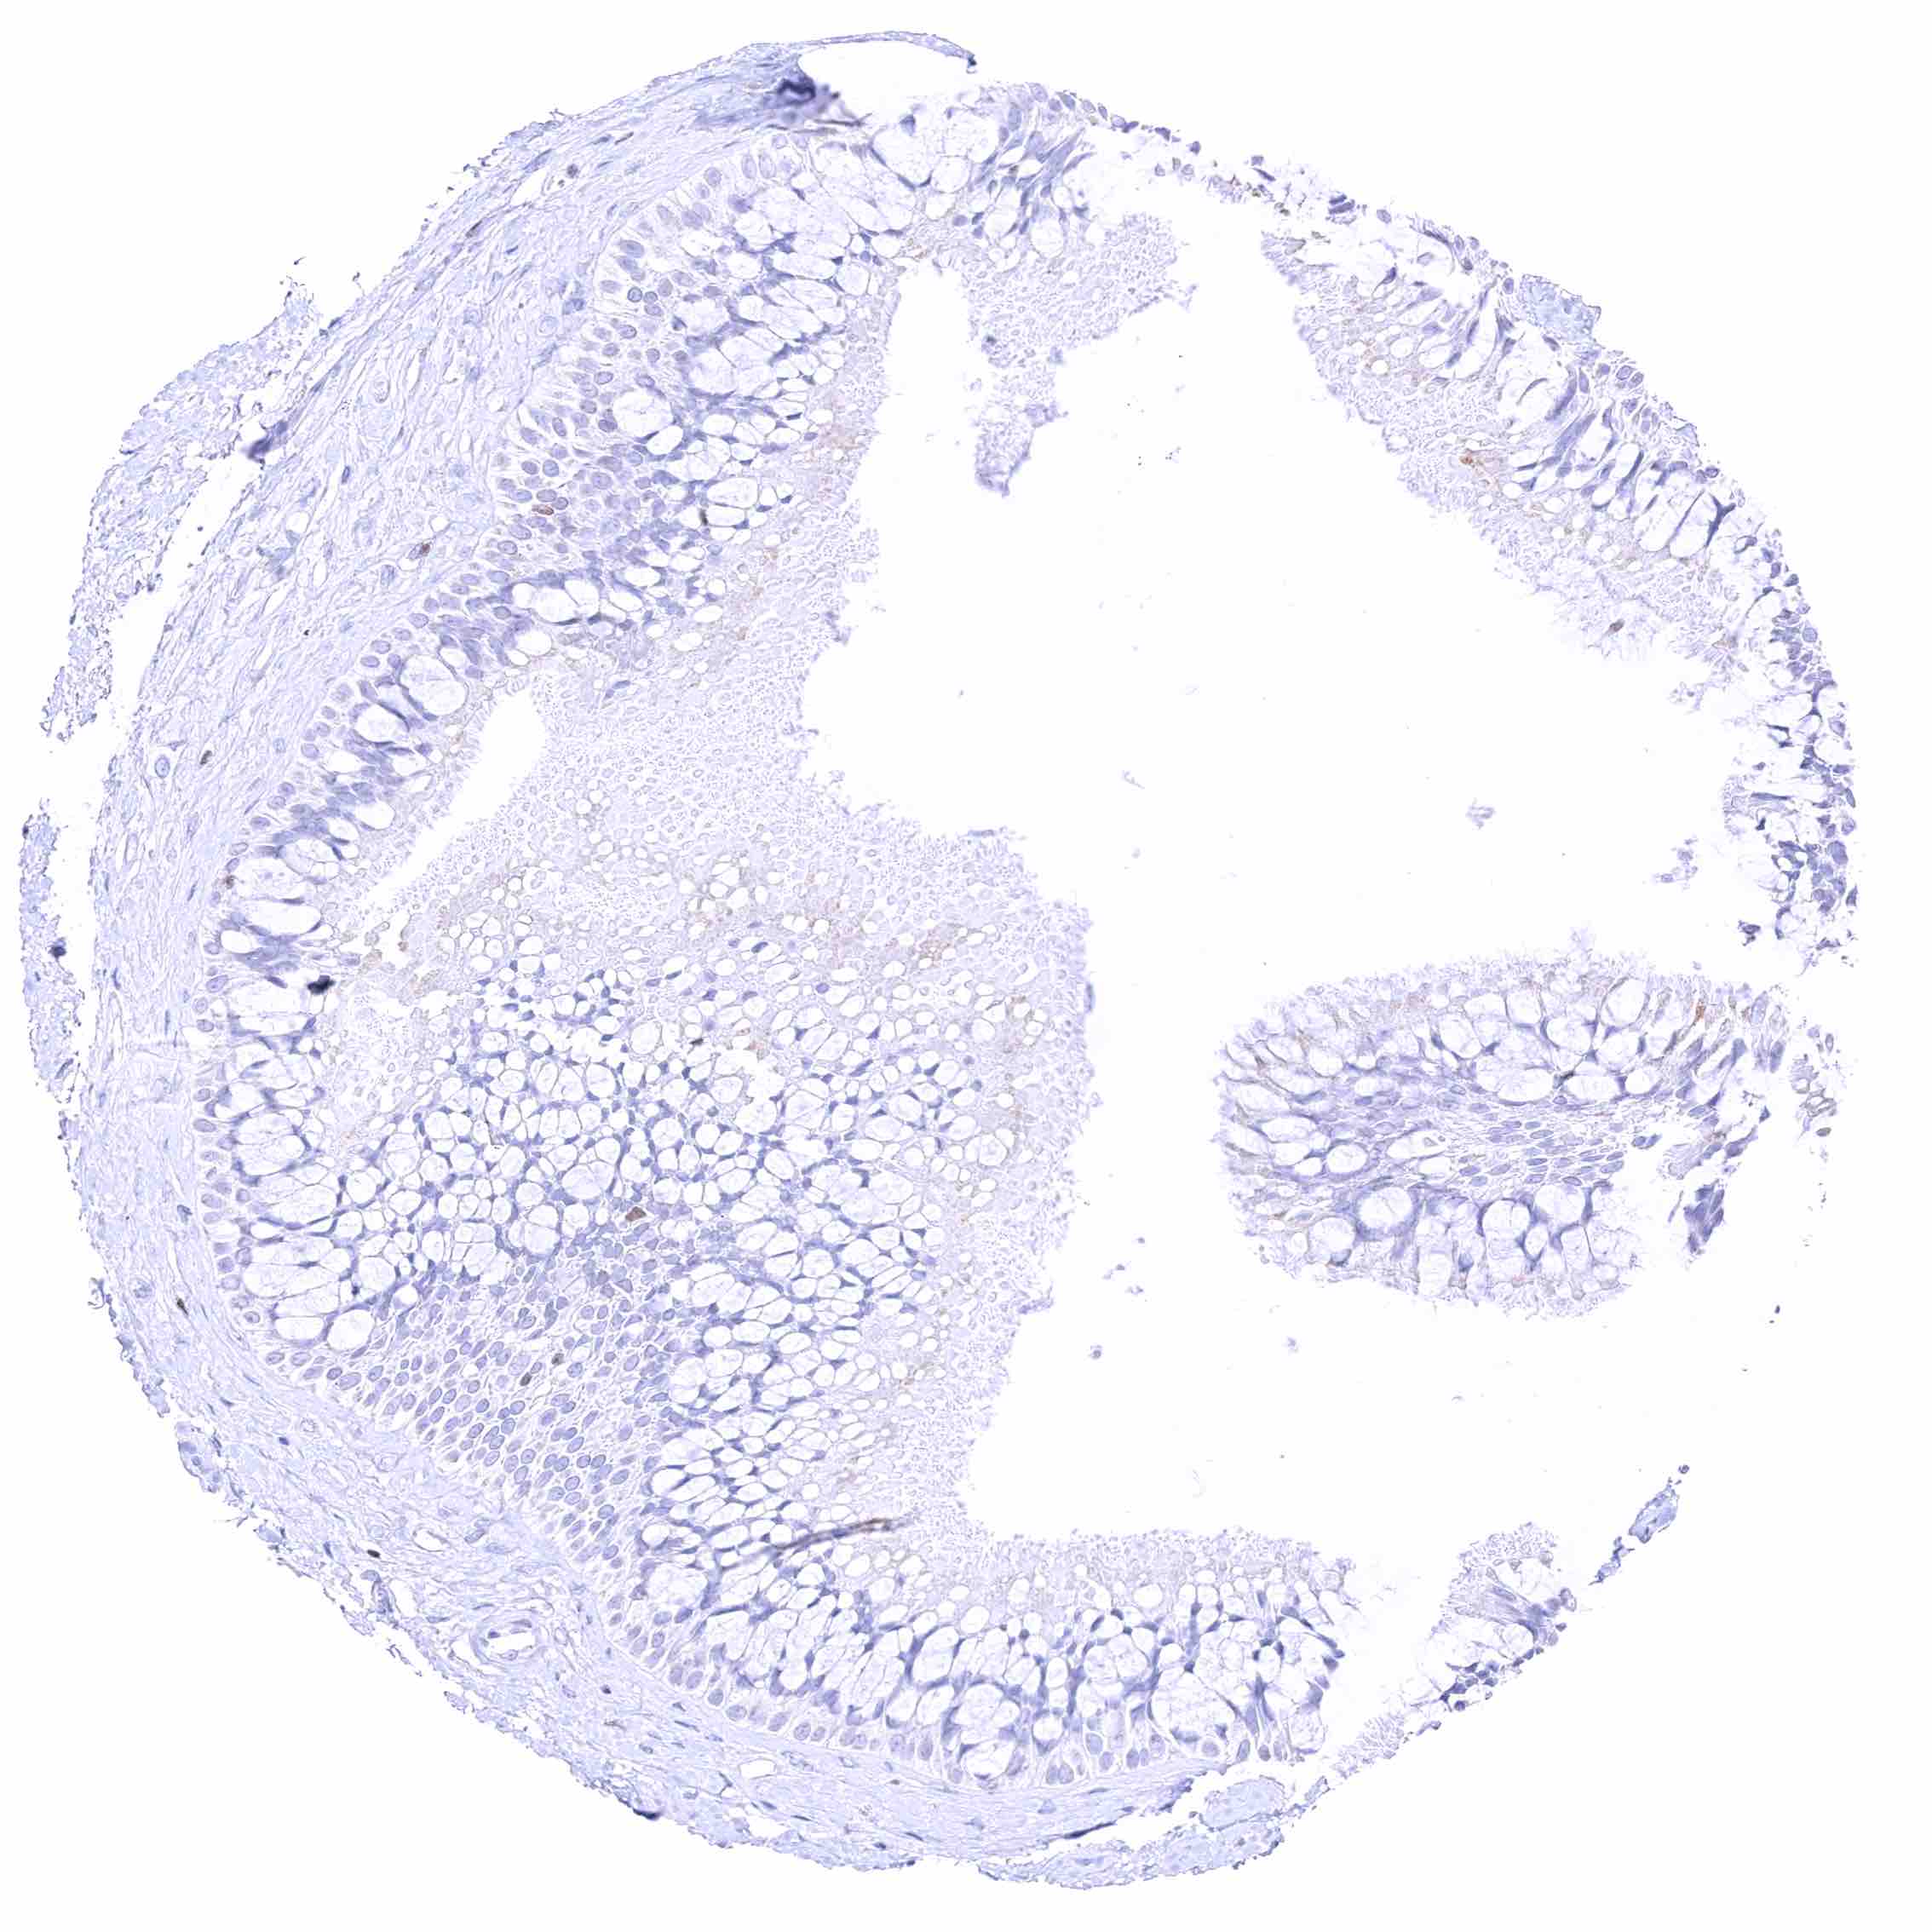

Rectum, mucosa – Nuclear GATA3 positivity of many lymphocytes.

Rectum, mucosa – Nuclear GATA3 positivity of some lymphocytes. Granular cytoplasmic GATA3 staining of epithelial cells.